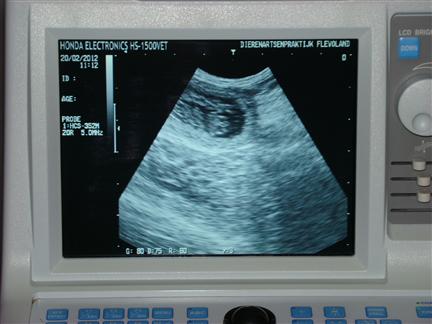

| FEEST, Fleur is drachtig, hier zie je één van de pupjes in wording |

in de donkere vlek (het vruchtwater) zie je een puppy |

| Je kon het hartje ook al fanatiek zien kloppen |

op basis van de ontwikkeling van het hartje is de uitgerekende datum op 22 maart 2012 vastgesteld |